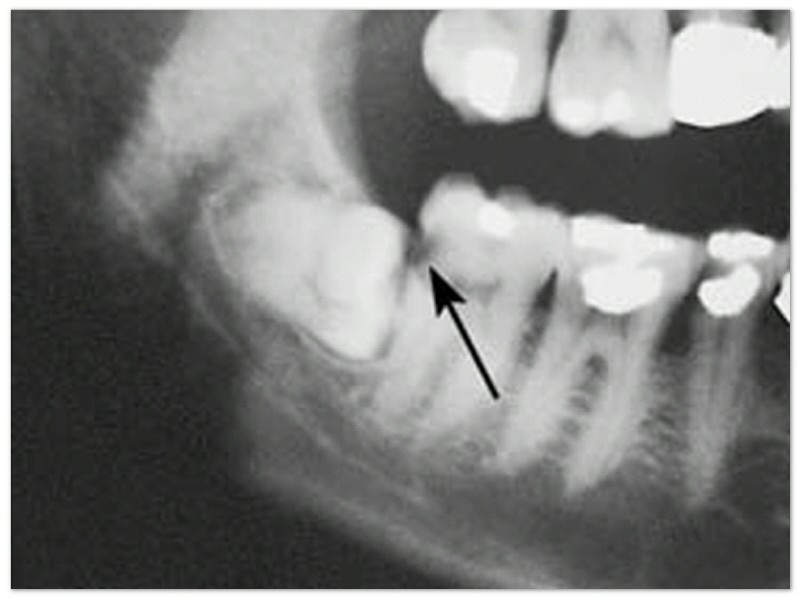

Gigi berlubang.

Gigi bungsu berada di paling belakang sehingga sering tidak terjangkau oleh sikat gigi. Akibatnya, banyak sisa makanan terjebak di sana dan menjadi penyebab gigi berlubang. Yang berlubang bisa gigi bungsu itu sendiri atau gigi di sebelahnya. Pasien sering kali tidak menyadari hal ini, tau-tau sudah sakit saja.

Merusak akar gigi sebelahnya.

Selain menyebabkan gigi berantakan, gigi bungsu yang arah tumbuhnya ke depan juga dapat menyebabkan gigi di sebelahnya menjadi rusak.